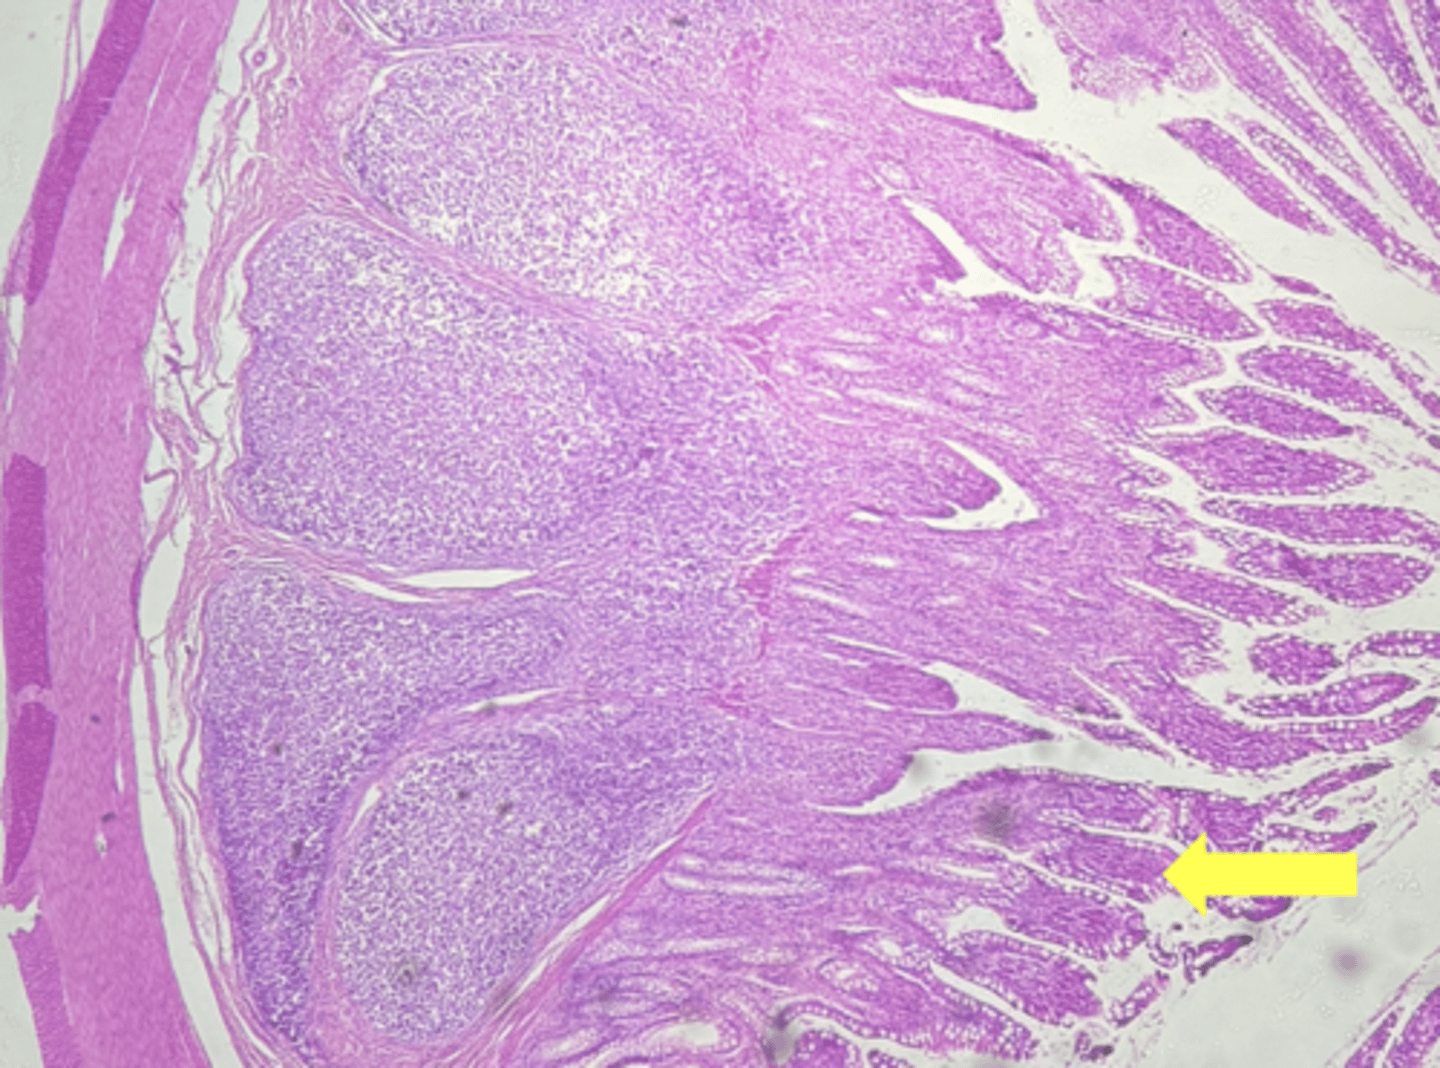

stomach

name the tissue

mucosa

(stomach)

submucosa

muscularis externa (3 LAYERS-KEY CHARACTERISTIC)

oblique layer

circular layer

longitudinal layer

simple columnar epithelium

gastric pits (KEY CHARACTERISTIC)

gastric glands (KEY CHARACTERISTIC)

Lamina propria

muscularis mucosae